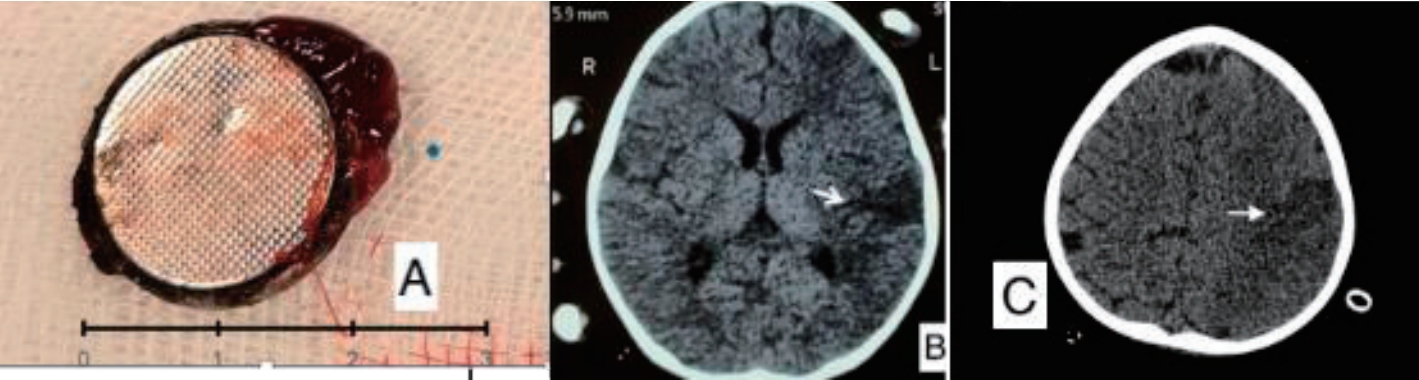

A previously well 18-month-old boy presented with 16 days history of poor feeding, fever and 2 episodes of clinically significant, well compensated upper gastrointestinal bleeding (UGIB) in the form of hematemesis and melena on day 10 and day 14 of illness respectively. He was transfused 2 units of packed red blood cells (PRBCs) elsewhere before presenting to us. On examination, the child was irritable, severely pale and had no splenomegaly. There was no history of witnessed foreign body ingestion. An urgent upper gastrointestinal endoscopy was performed after hemodynamic resuscitation which revealed an impacted foreign body in the upper esophagus with surrounding ulcerated mucosa (Fig. 1A). X-ray showed envisioned halo sign suggestive of BB (Fig. 1B). Computed tomography angiography (CTA) showed proximal left common carotid artery (CCA) pseudoaneurysm (4.9 mm×4 mm) in close proximity to BB suggestive of vascular fistula (Fig. 1C and D). Surgical consult was sought and BB removal was planned in operation theatre (OT) with cardiovascular and thoracic surgery back-up. Meanwhile, the child had another bout of massive UGIB requiring PRBC transfusions. After stabilization, the child was taken to OT and exploration was done via median sternotomy incision. Intraoperative findings included impacted BB in cervical esophagus and inflamed esophagus densely adhered to pretracheal fascia, left carotid sheath and prevertebral fascia. Intraoperative bleeding was seen at level of CCA, vascular control was ensured by using running sutures. BB was retrieved by intraoperative endoscopy by using grasping forceps. It was a lithium BB (20 mm×20 mm) (Fig. 2A). Esophagectomy with cervical esophagostomy, decompressive gastrostomy and feeding jejunostomy were done. Following surgery, feeding was established via jejunostomy. However, the child had right hemiparesis. CTA-head showed infarct in left parieto-temporal region involving middle and anterior cerebral artery territory (Fig. 2B and C). It was attributed to intraoperative compromised cerebral circulation due to probable clamping of branch of CCA while ensuring vascular control. Postoperative, child had fever, so antibiotics were upgraded from first-line (cefotaxime, amikacin and metronidazole) to piperacillin-tazobactum and teicoplanin. Blood culture grew Enterococcus fecalis sensitive to teicoplanin and child responded. Fortunately, hemiparesis has improved over the next one month and the child is on full enteral feeds and has a plan to restore anatomy after 3 months.

Fig. 2.

(A) Retrieved button battery (20 mm×20 mm). (B and C) Computed tomography image of the head showing a left parietotemporal infarct (white arrow).